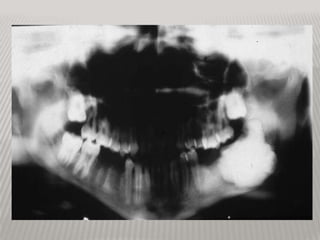

RADIOGRAPHIC FEATURES Early lesionsare radiolucent with smooth, well-defined contours. Later a well-defined radiopaque appearance develops. Most odontomas are small and do not exceed the size of a normal tooth in the region. However, large ones do occur and these may cause expansion of the jaw. Most odontomas are asymptomatic and as a result are discovered upon routine radiographic examination.

• 11.

RADIOGRAPHIC FEATURES *Odontomas mayblock the eruption of a permanent tooth and in these cases are often discovered when “searching for” the “missing” tooth radiographically. *They can be associated with impacted, malposition, malformation, and displacement of adjacent teeth.

COMPLEX ODONTOMA RADIOGRAPHICLLY Common lesions that persist through life  Usually detected in adolescence  most commonly in mandibular molars  not painful, or swelling  radiographically "sunburst radiopacities, thin uniform radiolucent rim  similar description as osteosarcoma, but assoc w/ tooth, clear of bony borders

• 15.

large radioopaque lesion • well encapsulated w/ radioiolucent border

COMPOUND ODONTOMA RADIOGRAPHICLLY *Most common odontogenic tumor *Appears as a cluster of multiple abortive teeth *Often prevents normal tooth eruption *Radiographically multiple tiny toothlike structures are contained within a fine radiolucent rim *Do not recur after excision *thus discovered during adolescence Histology of compound odontomas approaches normal tooth strcture. Gross clinical examination usually is sufficient for diagnosis.